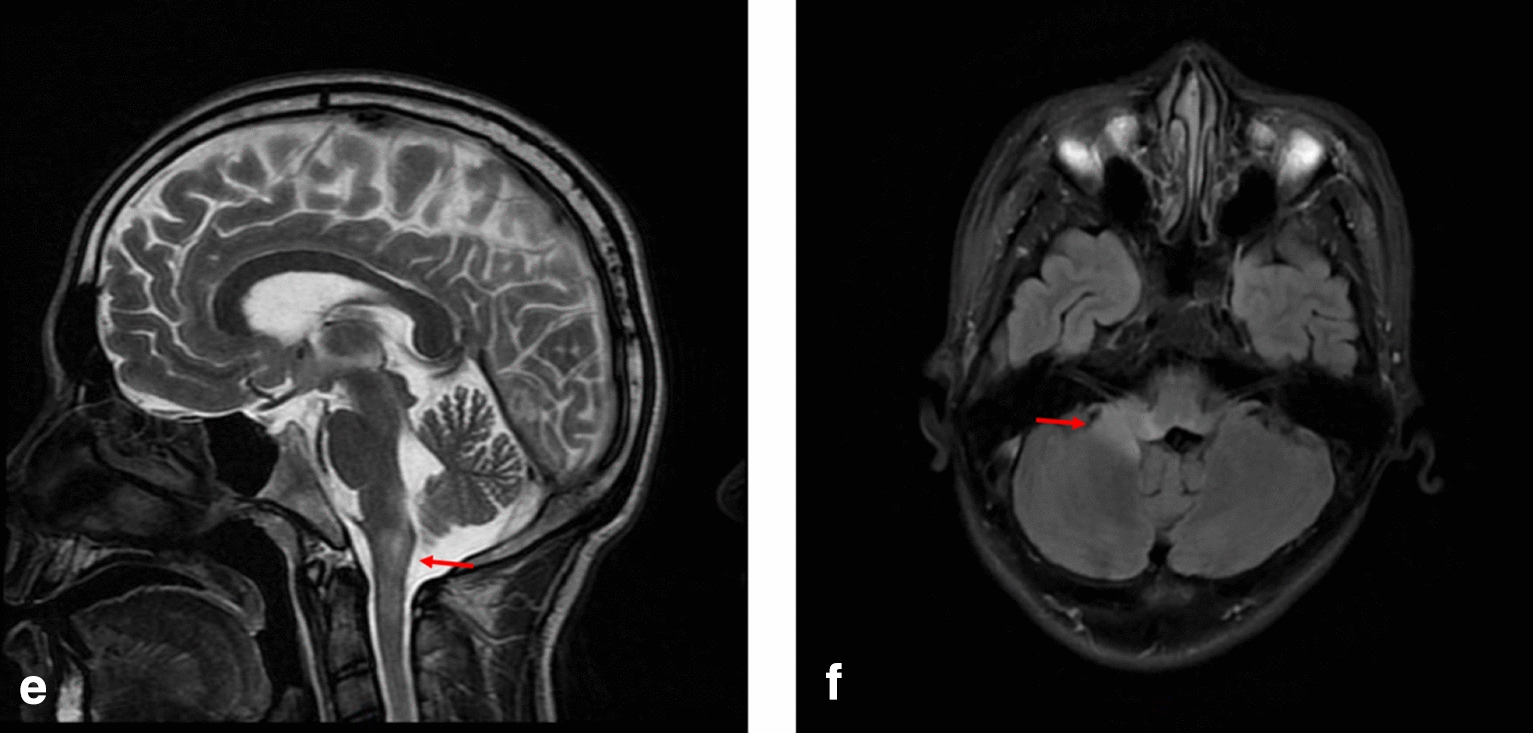

Fig. 3.

MRI T2 sequence of case 3 showing hyperintense in medulla oblongata (highlighted by arrows) in the e sagittal planes, and hyperintense in the right cerebellum and brainstem in the f transverse planes